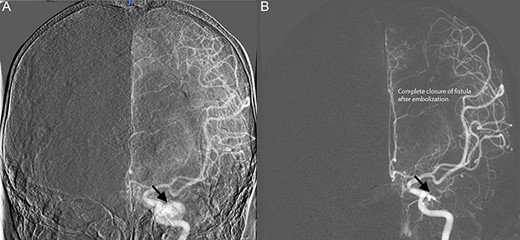

Diagnostic cerebral angiogram demonstrative of left indirect CCF. (A) Left ICA angiogram revealed a type B CCF supplied by branches of the meningohypophyseal trunk with inferior venous drainage (B) with evidence of subsequent spontaneous resolution.

Diagnostic cerebral angiogram (DCA) revealed bilateral indirect CCFs (type D on the right, type B on the left) with significantly higher flow on the right compared to the left (Figs 1C, 2A, 3A). A day later, through micro puncture of the right common femoral artery, coil was advanced (under real-time sonographic guidance and DCA). A microcatheter was used to access the right cavernous sinus via the left cavernous sinus through the intercavernous sinus. Right indirect CCF with arterial feeders arising from both the internal and external carotid arteries with outflow through the intercavernous sinus was confirmed. Embolization of the right cavernous sinus and intercavernous sinus was performed with 11 detachable coils and resolution of the type D carotid-cavernous flow was immediately noted (Fig. 2B); spontaneous resolution of the left type B CCF was noted (Fig. 3B) over a 24-h period of time.